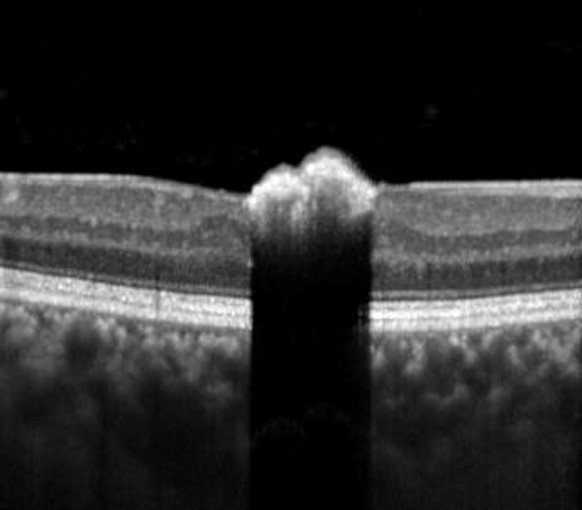

OCT imaging shows an elevated hyper-reflective lesion within the inner retina with deep posterior optical shadowing.